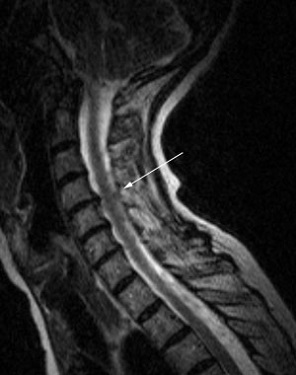

La HD cervicale consiste en l'expulsion d'un fragment de disque dans le canal médullaire. En cas de conflit avec les racines nerveuses ou la moelle épinière, des symptômes douloureux sont ressentis dans les épaules, bras ou mains. On parle alors de nevralgies cervico-brachiales.

L'arthrose cervicale consite en une "usure" des articulations. Des excroissances osseuses appelées "ostéophytes" peuvent apparaitre. S'ils sont trop développés, ils peuvent rétrécir le diamètre du canal et de foramens, comprimant des racines nerveuses ou la moelle epinière. Des symptômes douloureux sont ressenti dans les épaules, bras ou mains. On parle alors de névralgies cervico-brachiales.

La discopathie est le terme utilisé pour qualifier un disque intervertébral "usé". Les disques s'altérent avec le temps, ils se "déshydratent" et perdent une partie de leurs propriétés mécaniques. Dans certains cas, cette dégradation est sévère ou rapide, sur un ou plusieurs niveaux, pouvant entrainer des douleurs cervicales.